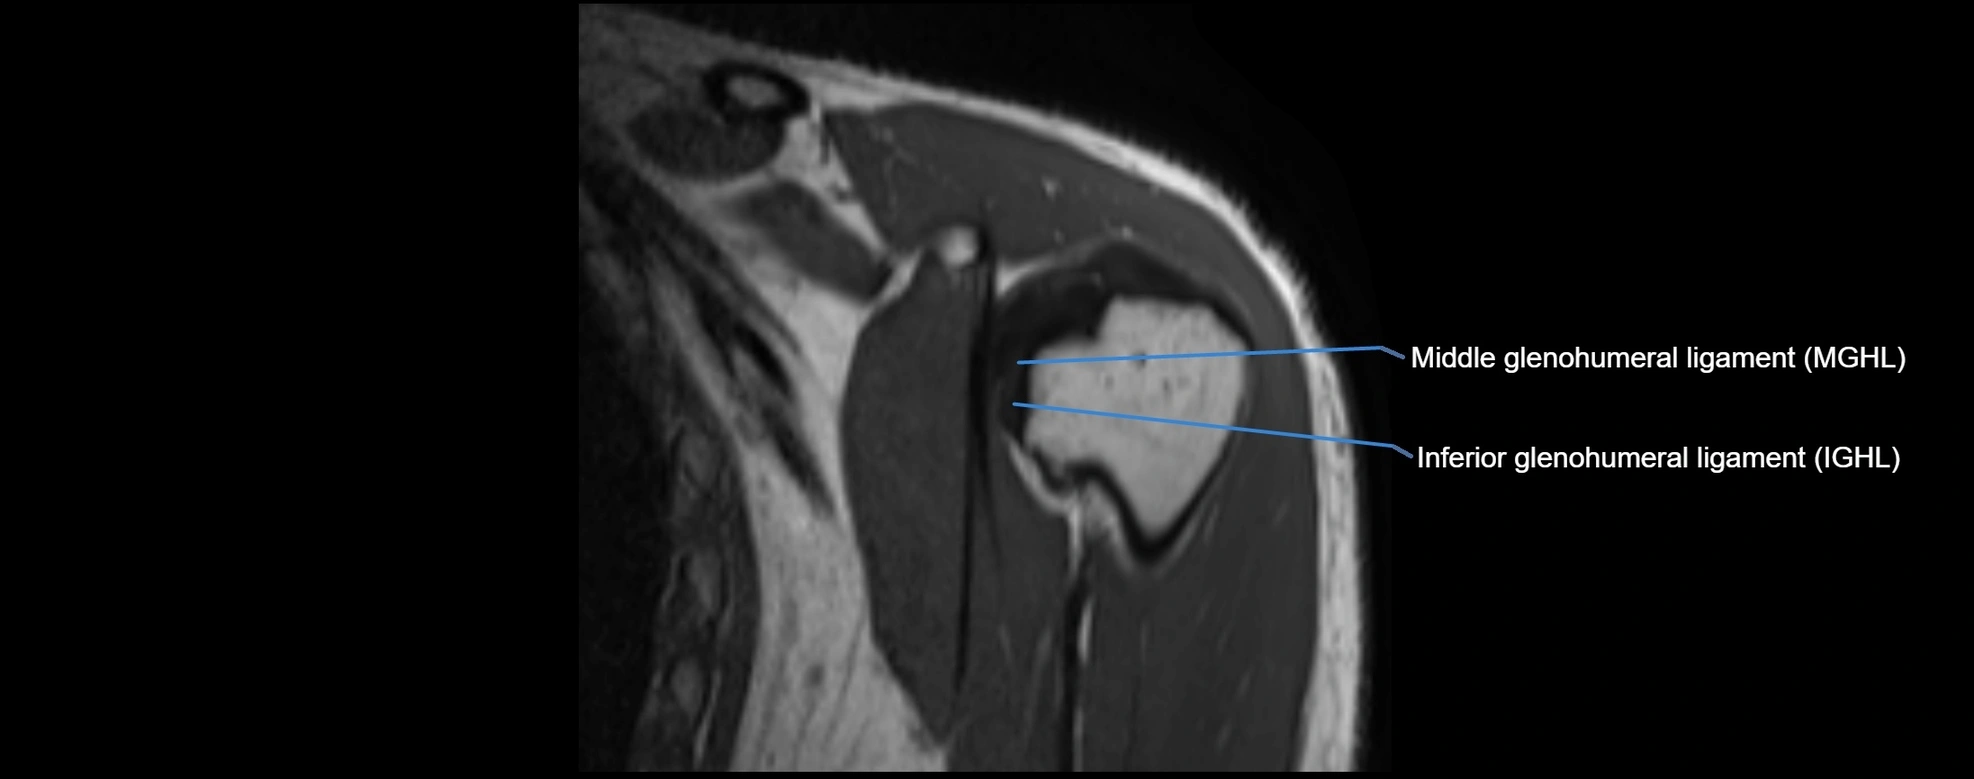

CT image

image